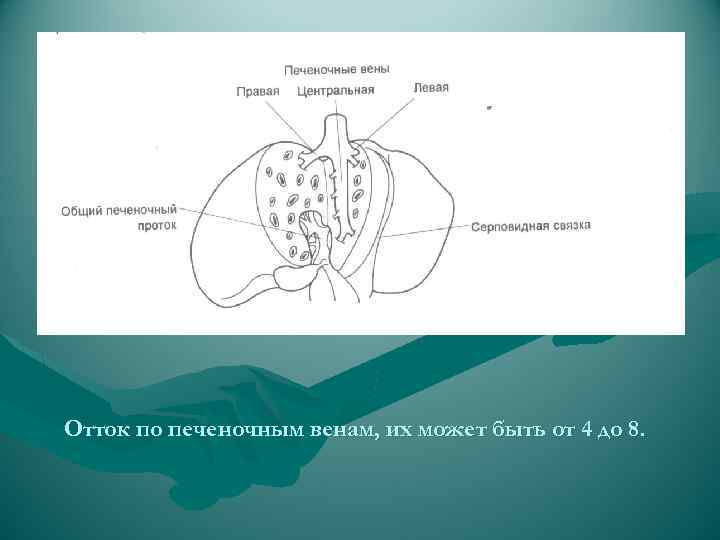

Отток по печеночным венам, их может быть от 4 до 8.

Отток по печеночным венам, их может быть от 4 до 8.